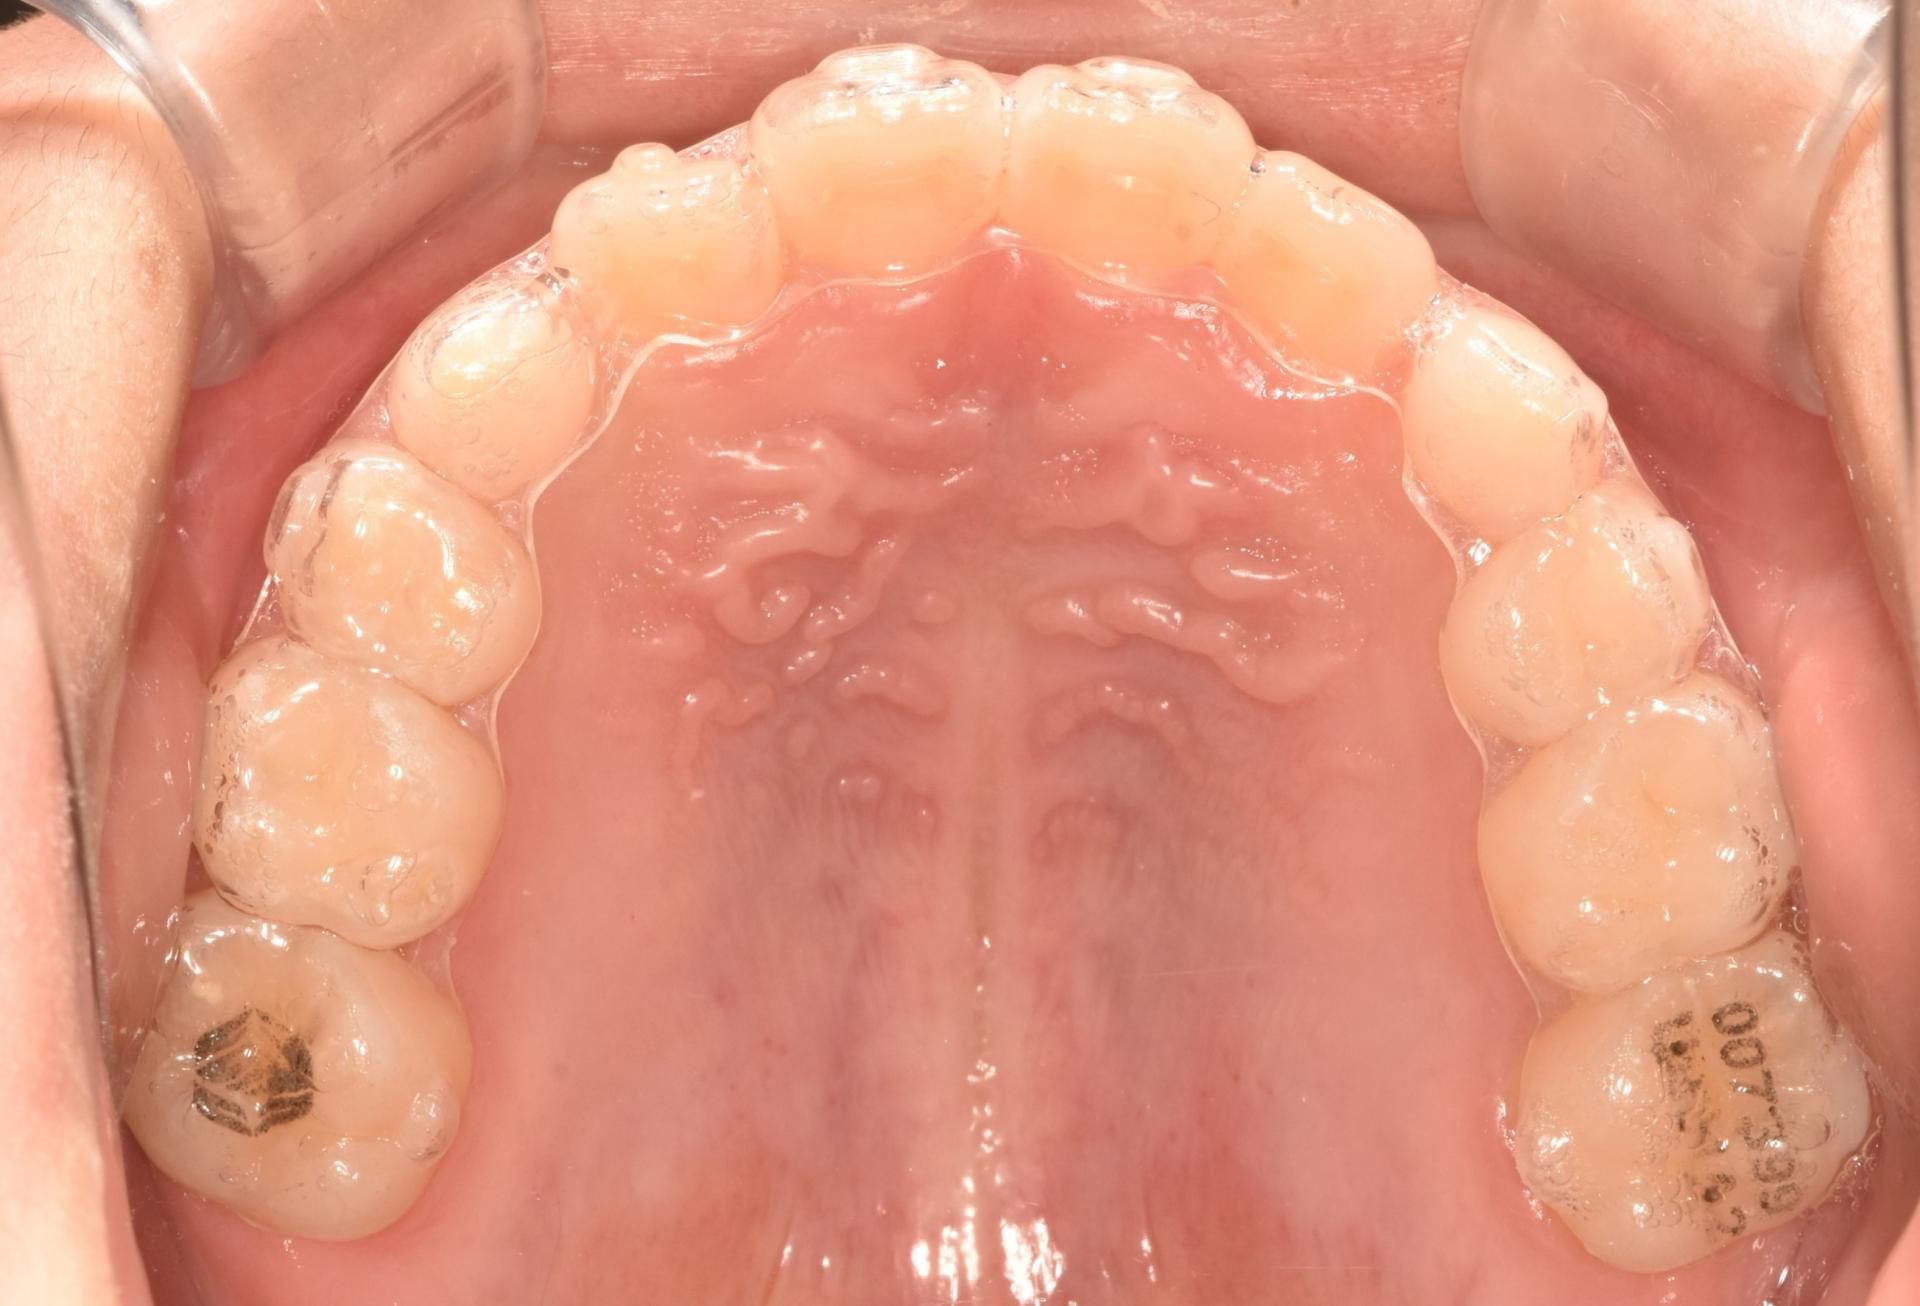

교정 진행중, 투명교정장치를 착용한 모습입니다. 치아위로 철사가 지나가지 않으니, 교정하는 것이 남들 눈에 띄지 않게, 편하게 뺏다 꼈다 하고, 철사 찔림이 발생하지 않으며 통증없이 치료를 진행할 수 있다는 장점이 있어 많은 어린이들이 선호하는 치료입니다!